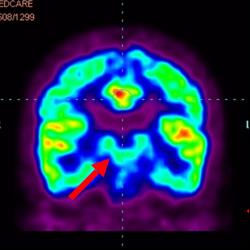

細(xì)胞治療后,藍(lán)色和黑色區(qū)域減少,并且看到更活躍的區(qū)域。這表明損傷減少并改善了大腦功能。